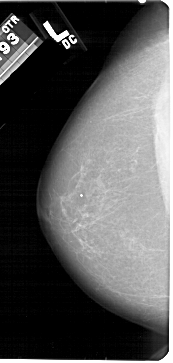

A_1428_1.LEFT_MLO

LEFT_CC LINES 5431 PIXELS_PER_LINE 2581 BITS_PER_PIXEL 12 RESOLUTION 43.5 NON_OVERLAY